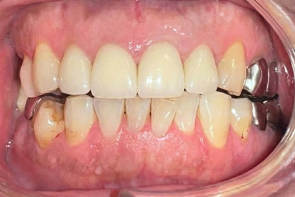

年間1,000症例以上の 「世界レベル」オペ実施

最安で税込99,800円~の低価格を実現